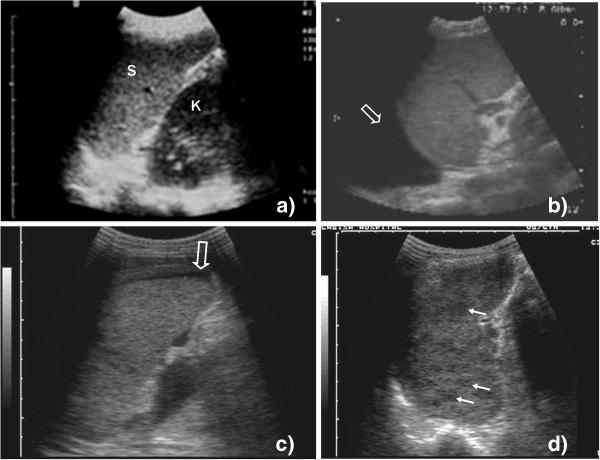

Ultrasound can rapidly identify abnormal signs, which in high prevalence settings, are highly suggestive of extra-pulmonary tuberculosis (EPTB). Unfortunately experienced sonographers are often scarce in these settings.

A protocol for focused assessment with sonography for HIV-associated tuberculosis (FASH) which can be used by physicians who are relatively inexperienced in ultrasound was developed.

The technique as well as normal and pathological findings are described and the diagnostic and possible therapeutic reasoning explained. The protocol is intended for settings where the prevalence of HIV/TB co-infected patients is high.